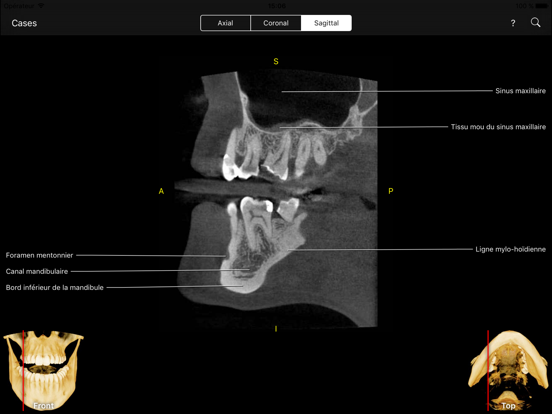

L’application CBCT permet aux cliniciens, résidents et étudiants en médecine dentaire d’apprendre les repères anatomiques de la même façon comme s’ils regardaient le volume via le logiciel de visualisation de données CBCT mais avec tous les repères visibles et animées sur toutes les vues MPR.

Le niveau d'interactivité et de visualisation est sans précédent. Cette application étonnante couvre des centaines de points de repère anatomiques visibles sur des volumes CBCT de petite à moyenne à grand champ de vue (FOV). Il vous permet également de tester vos connaissances à travers le mode test, ce qui est très "cool". Vous pouvez également rechercher un point d'intérêt ou le retrouver à partir d'une liste alphabétique et l'application vous l’indiquera.

- Plans de vue axial, frontal et sagittal.